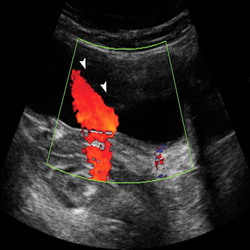

Ultrasonography Services